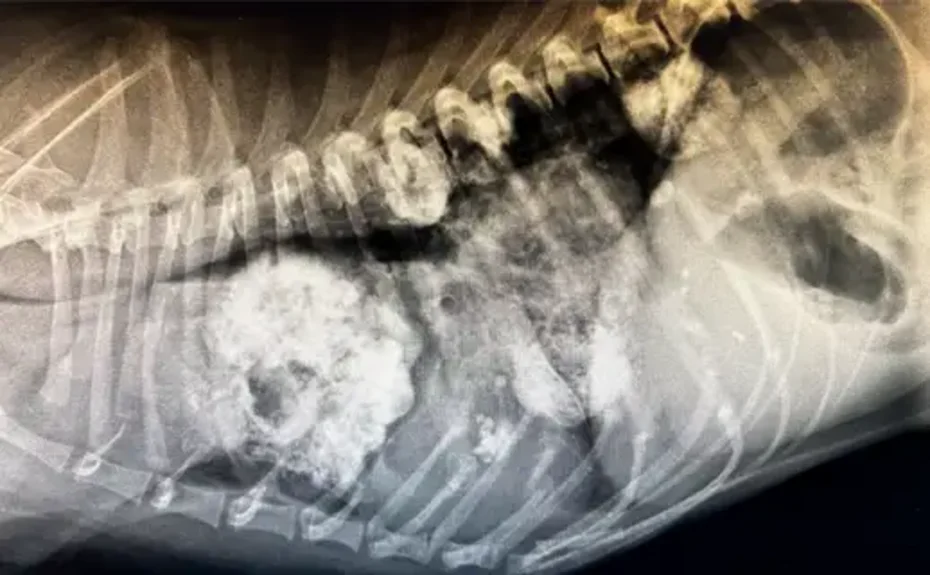

Onkologie

Die Diagnose- und Behandlungsmöglichkeiten haben sich auch im Fachbereich der Veterinärmedizin in den letzten Jahren schnell entwickelt. Mit Hilfe verschiedener Methoden versuchen wir die Lebensqualität Ihres Tieres zu steigern.